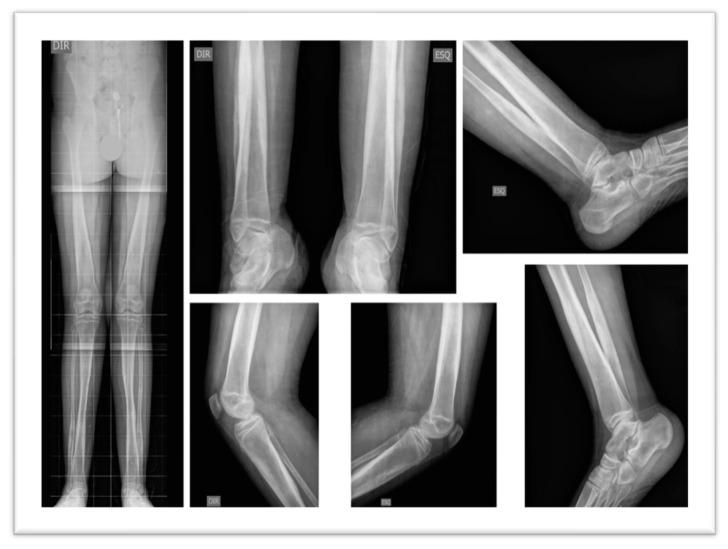

Camurati-Engelmann Disease (CED), or Progressive Diaphyseal Dysplasia, is a rare autosomal dominant disorder caused by heterozygous mutations in the Gene, essential for bone regeneration. This study examines the genotype-phenotype relationship in a family diagnosed with CED, specifically focusing on a missense variant (c.653G>A, p.Arg218Cys). The family comprised a mother and her two children, all of whom were found to carry the same disease-causing variant. The second child exhibited severe symptoms by age six, including progressive weakness and joint pain, leading to wheelchair dependency. The mother displayed milder symptoms with preserved independence. The firstborn son, initially asymptomatic, developed gait abnormalities and pain during adolescence. Clinical evaluations revealed characteristic hyperostosis of long bones, with significant variability in symptom onset and severity among family members, potentially indicative of genetic anticipation. This case underscores the importance of genetic testing and interdisciplinary management in CED, as traditional treatments, including corticosteroids and NSAIDs, often yield limited efficacy and notable side effects. Our findings contribute to the understanding of CED's pathophysiology and highlight the necessity for tailored therapeutic approaches. The identification of the common variant in this family reinforces the critical role of in bone metabolism and suggests avenues for further research into targeted therapies. Such reports enhance awareness and provide valuable insights for healthcare professionals managing rare genetic disorders.

卡姆鲁蒂-恩格尔曼病(CED),又称进行性骨干发育不良,是一种罕见的常染色体显性遗传疾病,由 基因的杂合突变引起,该基因对骨再生至关重要。本研究对一个确诊为 CED 的家族进行了基因型-表型关系研究,重点关注一种错义变异(c.653G>A,p.Arg218Cys)。该家族包括一位母亲和她的两个孩子,他们均携带相同的致病变异。第二个孩子在 6 岁时表现出严重的症状,包括进行性无力和关节疼痛,导致需要依赖轮椅。母亲的症状较轻,保持了独立性。长子最初无症状,但在青春期出现步态异常和疼痛。临床评估显示长骨有特征性的骨过度生长,家庭成员的症状起始和严重程度存在显著差异,可能提示遗传早现。该病例强调了 CED 中基因检测和多学科管理的重要性,因为传统的治疗方法,包括皮质类固醇和 NSAIDs,通常疗效有限,且副作用明显。我们的研究结果有助于了解 CED 的病理生理学,并强调了针对特定治疗方法的必要性。在这个家族中发现了常见的 变异,这进一步证实了 基因在骨代谢中的关键作用,并为针对该基因的靶向治疗研究提供了方向。此类报告提高了对管理罕见遗传疾病的医疗保健专业人员的认识,并提供了宝贵的见解。